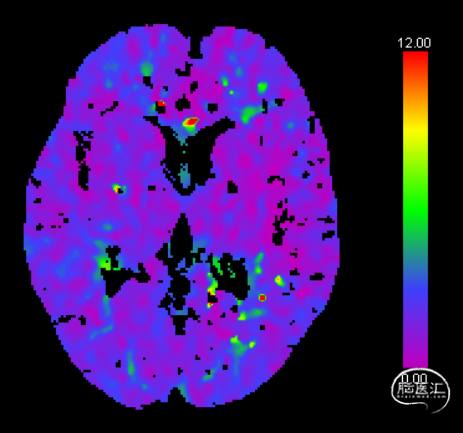

CTP CBF

CTP Tmax

Pre-OP CTP Tmax

Post-OP CTP Tmax

3、预后:对于合并狭窄的未破裂大型大脑中动脉夹层动脉瘤而言,重建夹层动脉瘤内血流+改善灌注是影响预后的关键。在本例患者中,采用一期狭窄段球囊扩张+血流导向装置治疗,未发生穿支血管缺血性事件,预后良好。